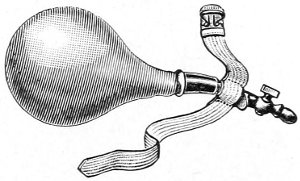

The examination of the uterus and other pelvic structures is often facilitated by dragging the uterus downward with a tenaculum while the vaginal or the bimanual examination is being made. Sensation in the cervix is so slight that little or no pain is experienced in this procedure. The anterior or posterior lip of the cervix is caught with the single or the double tenaculum (Fig. 4), guided along the vaginal finger or introduced through the speculum, and the uterus is drawn down by an assistant in case the bimanual examination is being made, or by the external hand of the examiner in case a simple vaginal examination is made. When this is done the utero-sacral ligaments are made tense, and can be felt like two cords extending from the sides of the cervix outward and backward to the pelvic wall. The posterior surface of the uterus can be palpated often as high up as the fundus. The method is especially useful when the examination is made by the rectum, and in this way the whole posterior surface and the fundus of the uterus may be palpated (Fig. 5).